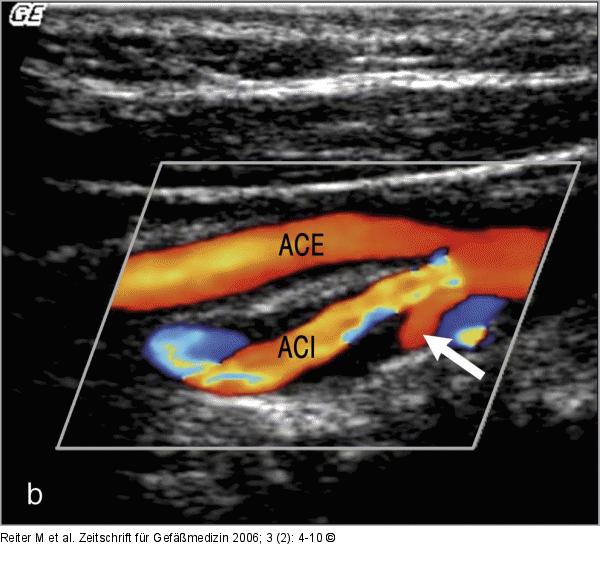

Abbildung 2a-c: B-Flow - Plaque Tief ulzerierte Plaque mittels B-Flow- (a), Farbdoppler (b) und i. a. DSA (c). (Z) zeigt das Ulkus. |

Abbildung 2a-c: B-Flow - Plaque

Tief ulzerierte Plaque mittels B-Flow- (a), Farbdoppler (b) und i. a. DSA (c). (Z) zeigt das Ulkus. |